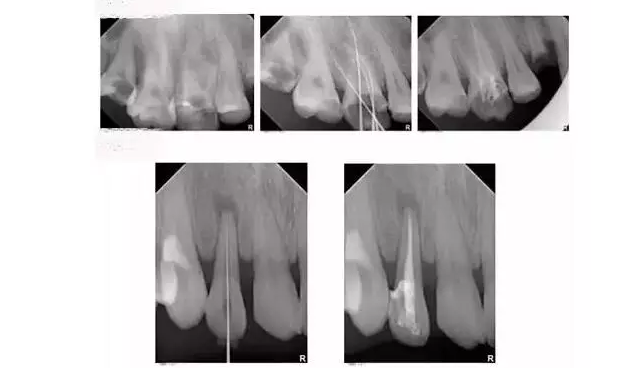

根管治療具體過程是怎樣的?

一般來說,根管治療需要就診2-4次,用時2-3周。

根管治療通常包括三個基本步驟:根管預(yù)備、根管消毒、根管填充。

4.png

首先會根據(jù)根管內(nèi)的炎癥牙髓和壞死物質(zhì),接下來測量根管長度,并適當(dāng)擴大根管(即根管預(yù)備過程)然后在根管內(nèi)封藥消毒,最后用藥物填充根管。

為什么根管治療需要拍多張片?

根管治療時,拍牙片是必要的,并且至少要保證3張牙片。

第一張:在治療前,幫助醫(yī)生了解牙根的基本情況,如根管預(yù)備是否到位等,并制定計劃。

第二張:在治療中,幫助醫(yī)生了解治療情況,如根管預(yù)備是否到位等,并指定下一步的計劃。

第三張:在治療結(jié)束后,幫助判定根管填充質(zhì)量,發(fā)現(xiàn)問題及時補救。